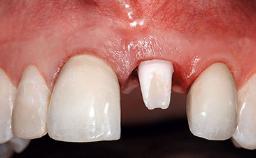

Replacement of an Ankylosed Upper Left Central Incisor: Bone Augmentation and Socket Grafting, Late Placement of an RC Bone Level Implant

Prosthesis Type FDP

SAC Level Advanced

Defining Characteristics One missing tooth to be replaced by an implant-borne crown